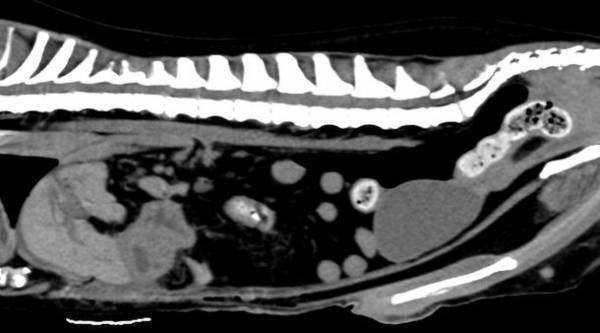

■CT検査

X線を用いて対象を360度方向から連続的に撮影することで全身の断層像を短時間で得ることができます。

得られる情報は非常に多く、悪性腫瘍の浸潤範囲や転移検索、臓器の形態的異常などを詳細に評価することができます。

CT検査画像

GE社製 64列128slice CT装置 Revoluion EVO